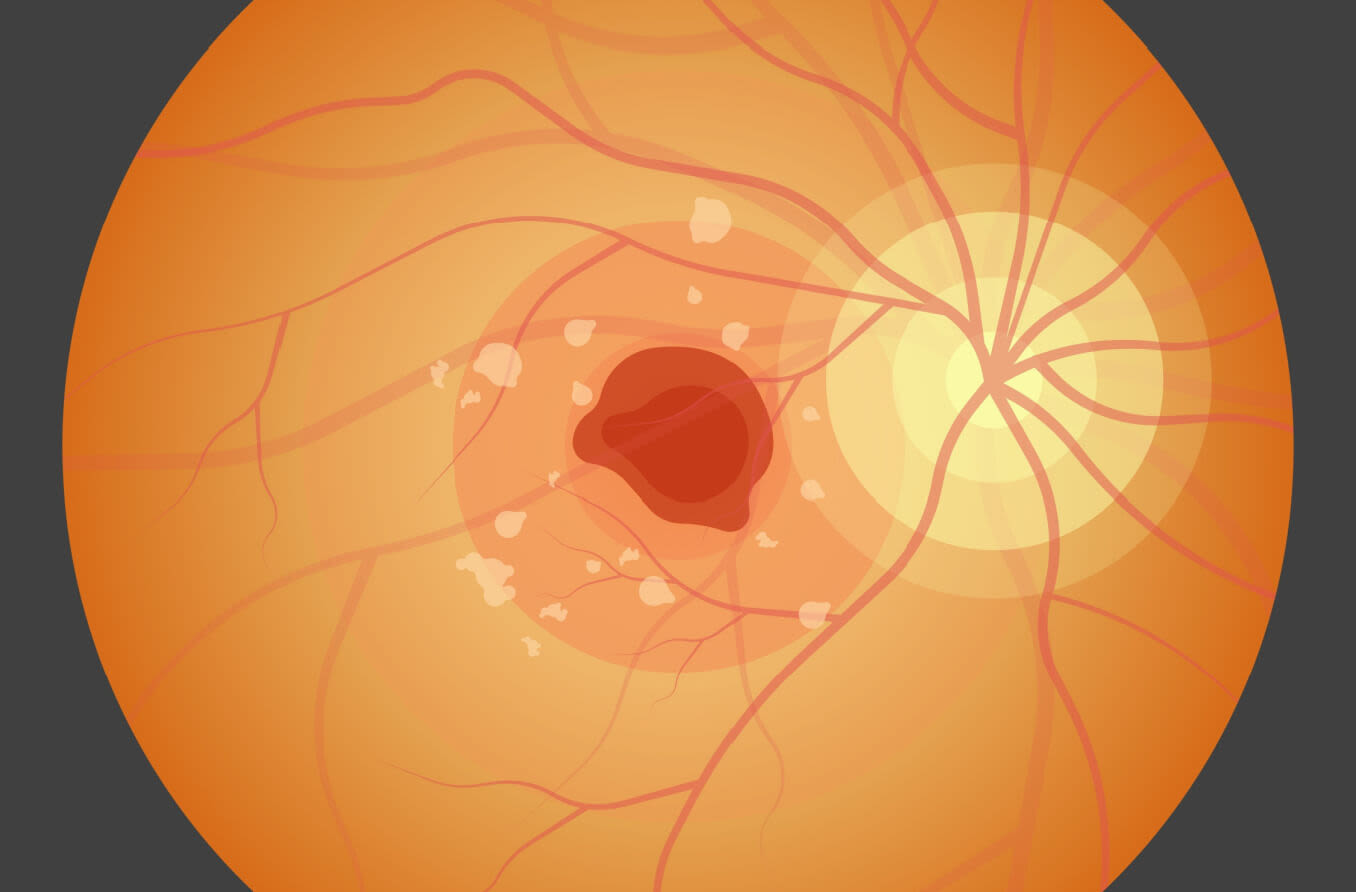

Stargardt generalmente se refiere a un grupo de enfermedades hereditarias que hacen que las células sensibles a la luz de la parte posterior interna del ojo (la retina) se deterioren, particularmente en el área de la mácula, donde ocurre el enfoque de precisión. También se produce pérdida de visión central, mientras que la visión periférica suele conservarse.

La enfermedad de Stargardt se diagnostica por la presencia de pequeñas manchas amarillentas de tejido en deterioro (drusas) desprendidas del recubrimiento coloreado o externo de la retina (epitelio pigmentario de la retina). La pérdida progresiva de la visión acaba llevando a la ceguera en la mayoría de los casos.

Los síntomas de la enfermedad de Stargardt pueden incluir visión borrosa o distorsionada, incapacidad para ver en condiciones de poca luz y dificultad para reconocer rostros conocidos. En las últimas fases de la enfermedad de Stargardt, también se puede perder la visión del color.